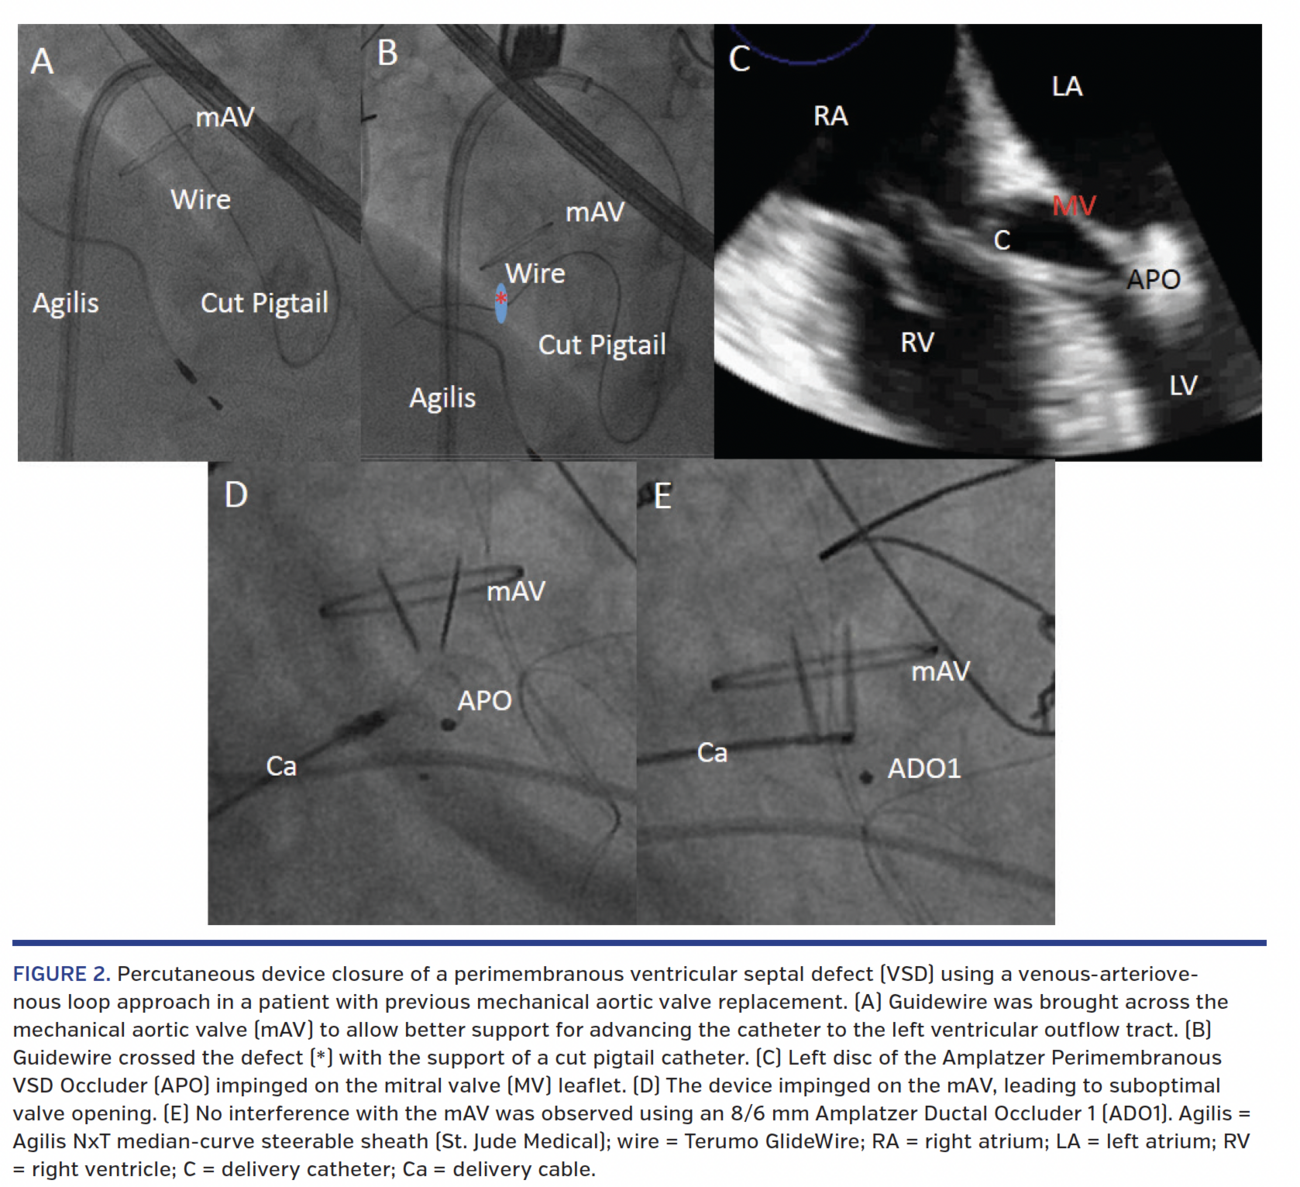

The presence of a mechanical aortic valve made the traditional arteriovenous loop by retroaortic approach less preferable due to potential risk of catheter entrapment and hypotension. Attempts to cross the VSD from the right ventricle (RV) with a hydrophilic guidewire failed despite the use of a steerable Agilis catheter (St. Jude Medical), largely because of the unfavorable angulation and high-velocity left-to-right jet. Hence, we performed transseptal puncture and the left ventricular (LV) angiogram showed a funnel-shaped defect with smaller waist on the RV side (Figure 1B). The VSD was then crossed from the LV side and a novel venous-arteriovenous loop was established (Figures 2A and 2B; Videos 2 and 3). A 12 mm Amplatzer Perimembranous VSD Occluder (St. Jude Medical) was first chosen to close the defect (Video 4). During pull-back toward the VSD, the left-sided disc of the device inadvertently impinged the mitral valve leaflet, causing profound hypotension, which resolved after release of the tension in the delivery system (Figure 2C). In addition, the mechanical aortic valve leaflet motion was jeopardized due to device interference immediately after deployment (Figure 2D; Videos 5 and 6). Smaller 10 mm and 8 mm devices were tested with similar results. Finally, an 8/6 mm Amplatzer Ductal Occluder 1 (St. Jude Medical) successfully sealed the funnel-shaped defect (Figure 1G; Video 7). The device was pulled to better conform to the defect and thereby avoided interference with aortic valve function.